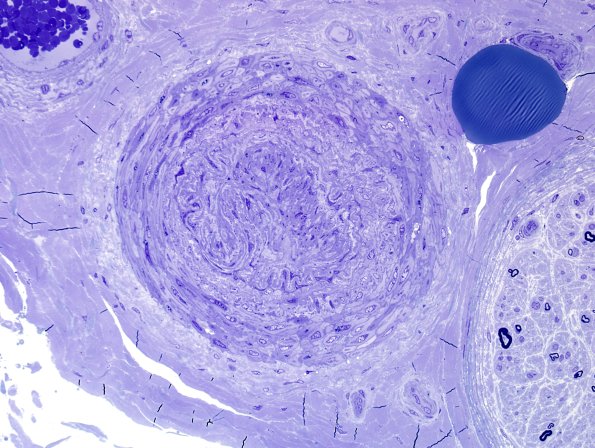

Washington University Experience | PERIPHERAL NEUROPATHY | 11 VASCULITIS - VASCULOPATHY | 1 Normal Vasculature | 3A4-Vessel-telescoped-Case-3B-Plastic-1.jpg

A different case in which the same telescoping artifact is prominent. (Plastic section)